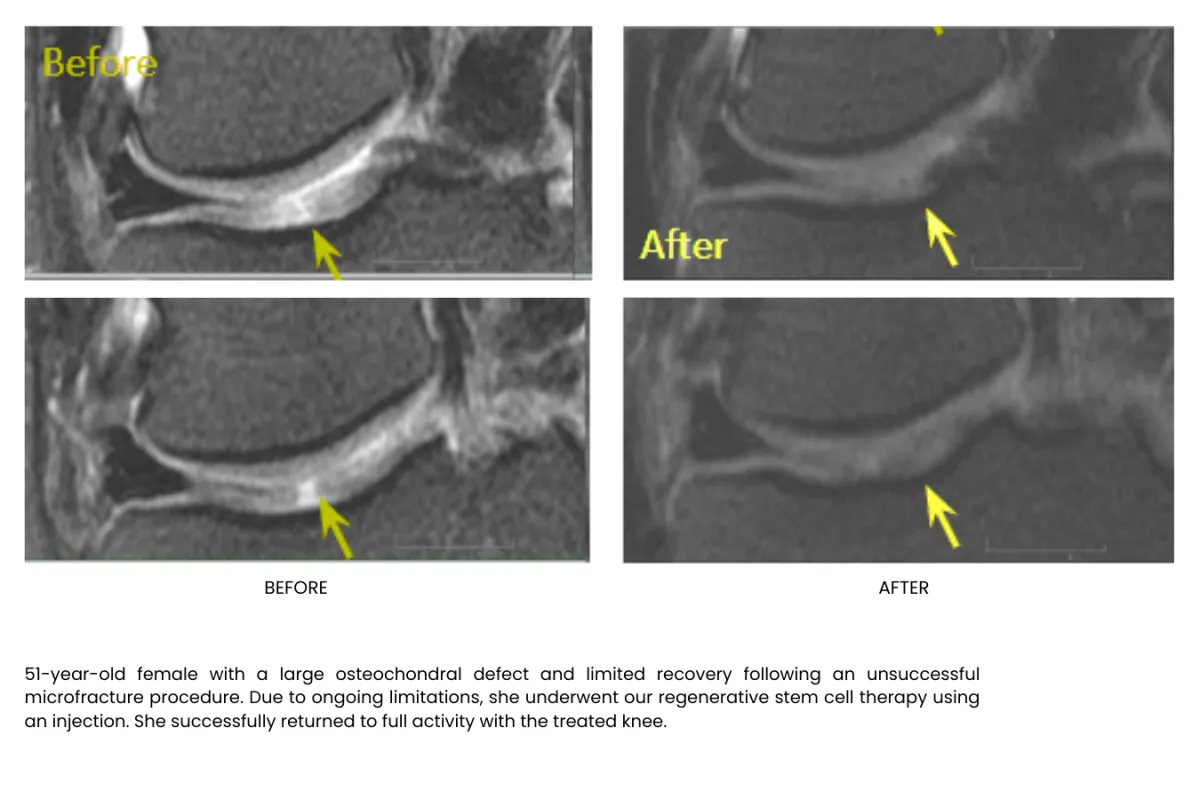

Millions of stem cells delivered precisely in the injured area building up tissue, recovering and freeing your from pain, without surgery or long recoveries.

Stem cell therapy is a regenerative treatment that uses specialized healing cells to help repair damaged tissue, reduce inflammation, and support your body’s natural healing process. It’s commonly used for joint pain, arthritis, and chronic musculoskeletal conditions.